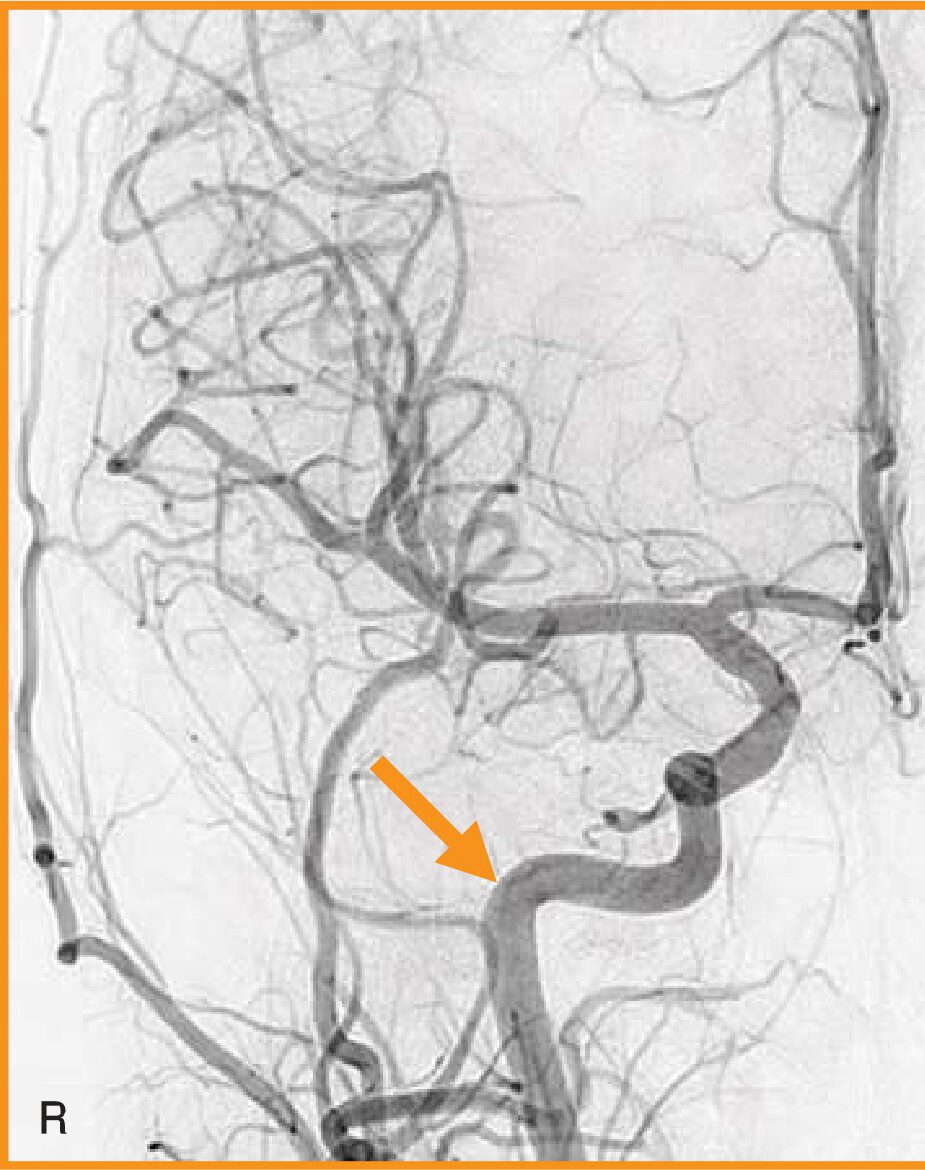

頭部の血管造影写真(別冊No.10)を別に示す。矢印で示すのはどれか。

- 1椎骨動脈

- 2内頸動脈

- 3脳底動脈

- 4浅側頭動脈

- 5中大脳動脈